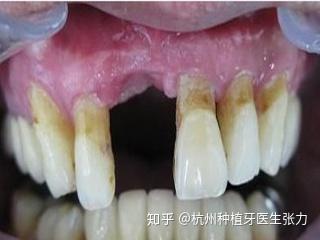

牙槽骨是人体的“活性骨”,缺牙后缺乏咀嚼刺激,会逐渐吸收萎缩,导致牙槽骨高度降低、宽度变窄,甚至出现“骨凹陷”,前牙区缺牙后,牙槽骨吸收可能影响牙龈美观;后牙区骨量不足则无法容纳种植体,部分患者因先天牙槽骨发育不良、肿瘤切除或外伤等原因骨缺损,也需通过骨粉植入重建骨结构。

- 专业洁治:每6个月进行1次种植体专业洁治,清除普通刷牙无法去除的菌斑和结石,预防种植体周围炎(牙龈炎症导致的骨吸收)。

- 观察牙龈状态:若牙龈出现红肿、出血、退缩或牙冠松动,需及时就医,避免炎症扩散影响种植体寿命。